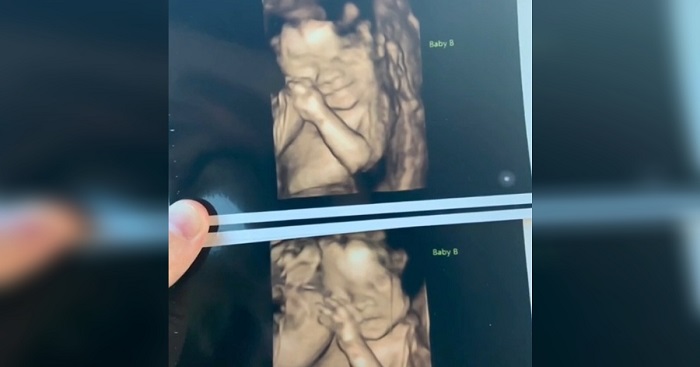

Combs already knew that her daughters were exceptional before she gave birth. Both Kennadi and Mckenli were Mono/Di twins. These types of twins are extremely rare, and both babies had their individual sacks inside her womb, yet they shared the same placenta. However, there was yet another twist to these twins’ story.